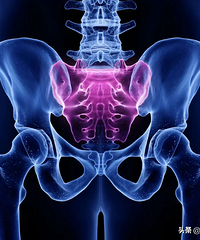

医生判断胎儿有没有入盆,就是靠这个手势……